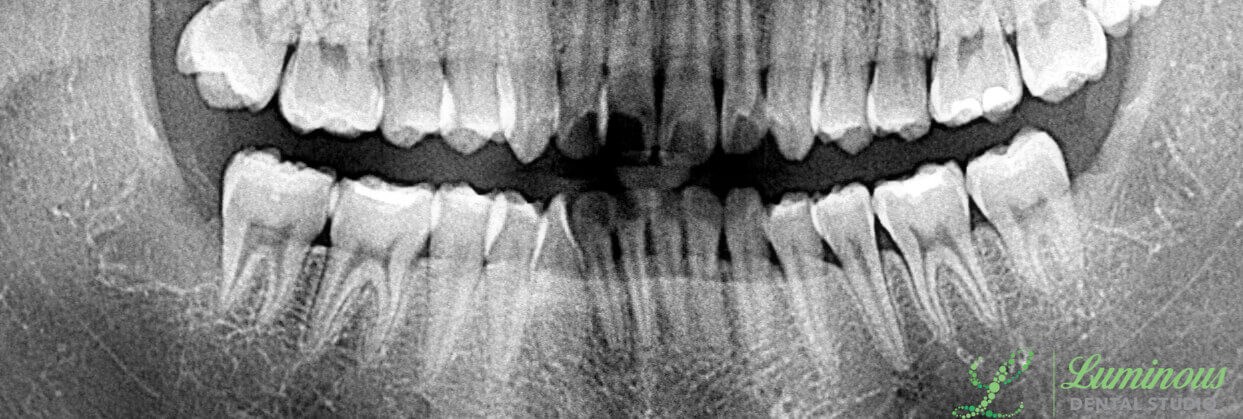

Your wisdom teeth (third molars) can cause some serious problems and damage to your overall dental health if you need to have them removed. Luminous Dental Studio offers nonsurgical and surgical wisdom teeth extractions with our experienced general dentists, Dr. Minho Chang and Dr. Nam Kim. When it is time to make the decision on how to take out the wisdom teeth, you can rely on our Luminous Dental Studio dentists to provide you with state-of-the-art technologies to diagnose the problem and to design a strategy that has your best interest at heart. We will capture your wisdom teeth in digital x-rays to check for signs of infection, what they are doing to the surrounding teeth and gums, and whether or not a bone will have to be removed to get an impacted wisdom tooth out. Our Luminous Dental Studio dentists, Dr. Chang and Dr. Kim, can extract troublesome teeth quickly and comfortably. Book your appointment to discuss tooth extractions.

Older children and young adults are the usual candidates for the removal of their wisdom teeth. The type of extraction you have is based on the health of each tooth. Some patients will qualify for a nonsurgical extraction (or traditional extraction) for removal. Candidates for the surgical removal of a wisdom tooth may already be experiencing dental problems, such as impaction, overcrowding, an infection, and more. There are several indications of an impacted tooth that will tell Dr. Kim or Dr. Chang how to proceed with the removal. If you do not have an impaction, you would make an ideal candidate for nonsurgical extraction. In the event that you have impacted third molars (even if they have not erupted out of the gumline), a surgical approach may be necessary.